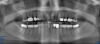

Fig 29. Preoperative Panorex.

Figure 29